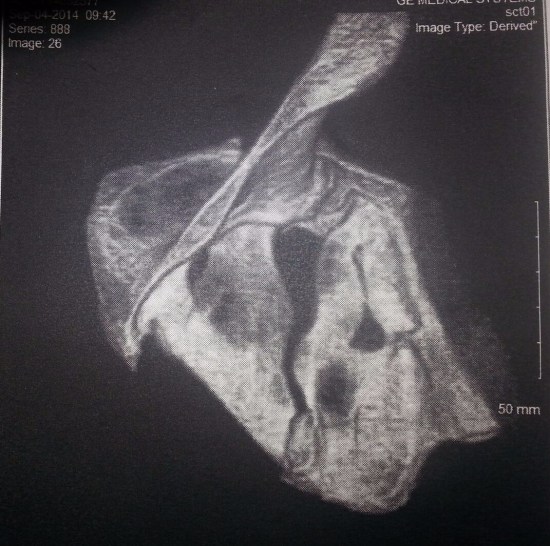

I am so eternally grateful for the No-Fault system. I sustained a Polytrauma which included multiple orthopedic fractures (5 in my spine alone, ribs, wrist, pelvis, scapula/shoulder, soft tissue injuries, nerve damage, and a traumatic brain injury).

Thanks to Auto No Fault I was able to have the necessary MULTIPLE xrays, CT Scans and lifesaving surgeries to help me survive. I had to go out of State to save the use of my arm due to a shattered scapula as we have no Trauma surgeons in Michigan who were trained to do that repair. Michigan No Fault made it possible for me not to lose all of the function in my right arm. My whole scapula and shoulder had to be rebuilt.

It is rare to fracture your scapula. In fact I did not just fracture mine, I shattered it. That gives you a bit of an indication of the sheer force involved with the wreck and how truly blessed I am to still be here to talk about this.